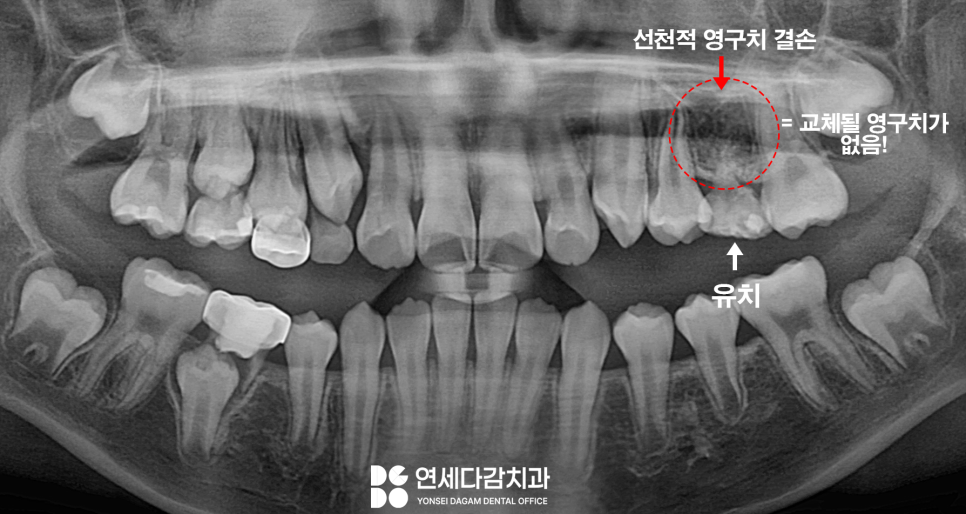

선천적 영구치 결손

이것은

태어날 때부터 영구치의 씨앗인 치배가

형성되지 않은 상태를 말합니다.

엑스레이 사진을 촬영해 봤을 때

탈락될 유치 밑으로

교체될 영구치가 올라오는 것이

보이는 게 정상입니다.

그러나 잇몸뼈 속에 있어야 할

영구치가 보이지 않는 경우,

선천적 영구치 결손이라 판단합니다.